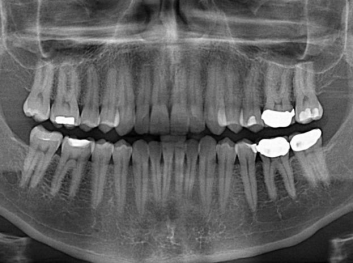

Adam Celiz,是來自諾丁漢大學的研究人員,他和同事開發(fā)的這種新型合成生物材料,能刺激干細胞在牙髓部的生長。與普通材料一樣,這種合成材料被填充到牙齒并用UV光硬化。

在體外測試中,材料刺激干細胞進入牙本質的增殖和分化速度,促進形成牙齒骨組織。研究人員認為,一旦材料在受損牙齒中應用,這些干細胞可以自動修復來自填充物上的損壞。在本質上,該生物材料將使牙齒自愈。